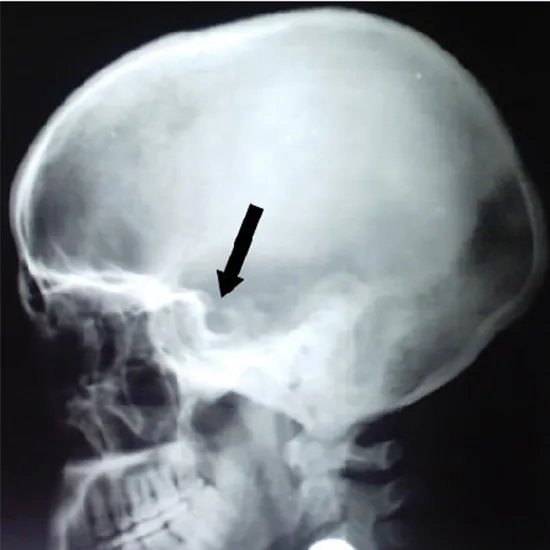

An X-ray of the head and neck The LAT cone view for sella is a non-invasive examination that does not cause pain or discomfort. It is used to see the pituitary gland or the sella turcica (on which the pituitary gland lies) and the soft tissues surrounding it (skin and muscles).

• To discover issues with your sella (reduced/flattened pituitary gland).

• To identify the existence of a pituitary tumor (cancer).

• To determine what causes hemianopsia (decreased vision).